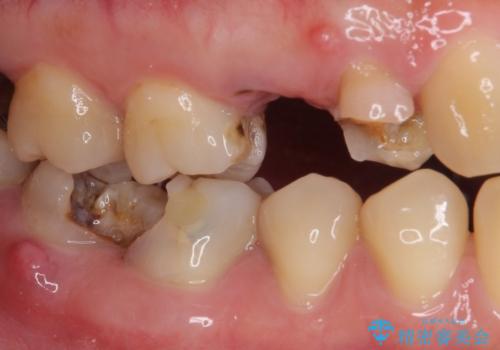

開咬により奥歯のみが接触している状態で、前歯部にほとんど接触のない状態で、奥歯に非常に負担のかかる咬み合わせでした。

また、欠損や根管治療の必要な歯など、むし歯による問題も多く散見されました。